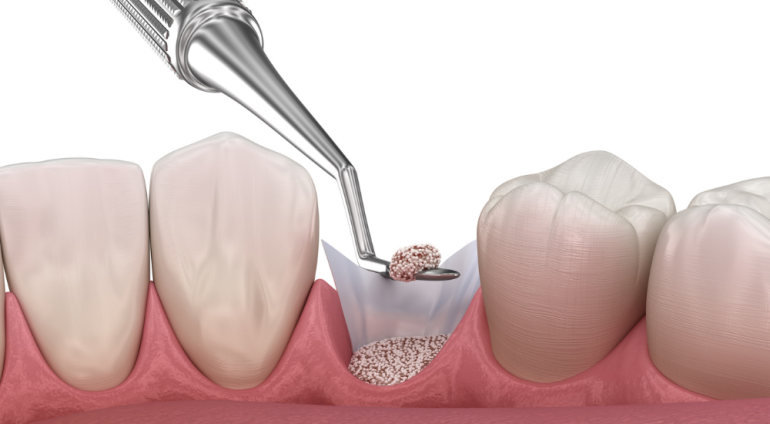

- 骨再生療法

骨再生療法:失われた骨を「再びつくる」

歯周病によって一度失われてしまった歯茎や顎の骨は、残念ながら自然に元通りになることはありません。しかし、近年進歩した骨再生療法を用いることで、まるで時間を巻き戻すかのように、失われた組織や骨の再生を促すことが可能になりました。この画期的な治療法によって、抜歯を回避し、ご自身の歯を残せる可能性が飛躍的に高まっています。

歯周病によって一度失われてしまった歯茎や顎の骨は、残念ながら自然に元通りになることはありません。しかし、近年進歩した骨再生療法を用いることで、まるで時間を巻き戻すかのように、失われた組織や骨の再生を促すことが可能になりました。この画期的な治療法によって、抜歯を回避し、ご自身の歯を残せる可能性が飛躍的に高まっています。

骨再生療法には、歯周病の進行度合いや骨の状態に応じた、主に以下の2つのアプローチがあります。

GBR法(骨誘導再生法)

GBR法は、歯周病によって骨が著しく不足している部位に、人工骨やご自身の顎から採取した骨(自家骨)を移植することで、骨の量を増やす治療法です。特殊なバリア膜(メンブレン)を使用して、骨が再生するための空間を確保し、その中に骨補填材を充填することで、骨の再生を誘導します。

GBR法も外科処置が必要となります。骨の量が少ない場合には吸収性の膜を、より多くの骨量が必要な場合には非吸収性の膜を使用します。非吸収性の膜を用いた場合は、骨が十分に再生した後、膜を除去するための簡単な再手術が必要となることがあります。

エムドゲイン法

歯周病によって部分的に失われた、歯を支える組織を回復する治療です。歯ぐきを切開し、失われた歯周組織の部分にエムドゲインという薬剤を塗布して縫合します。

赤い枠で囲まれた部分をご覧下さい。レントゲン写真では、組織が失われている部分が黒く写ります。治療後では、うっすらと白く写り、骨が再生していることが分かります。